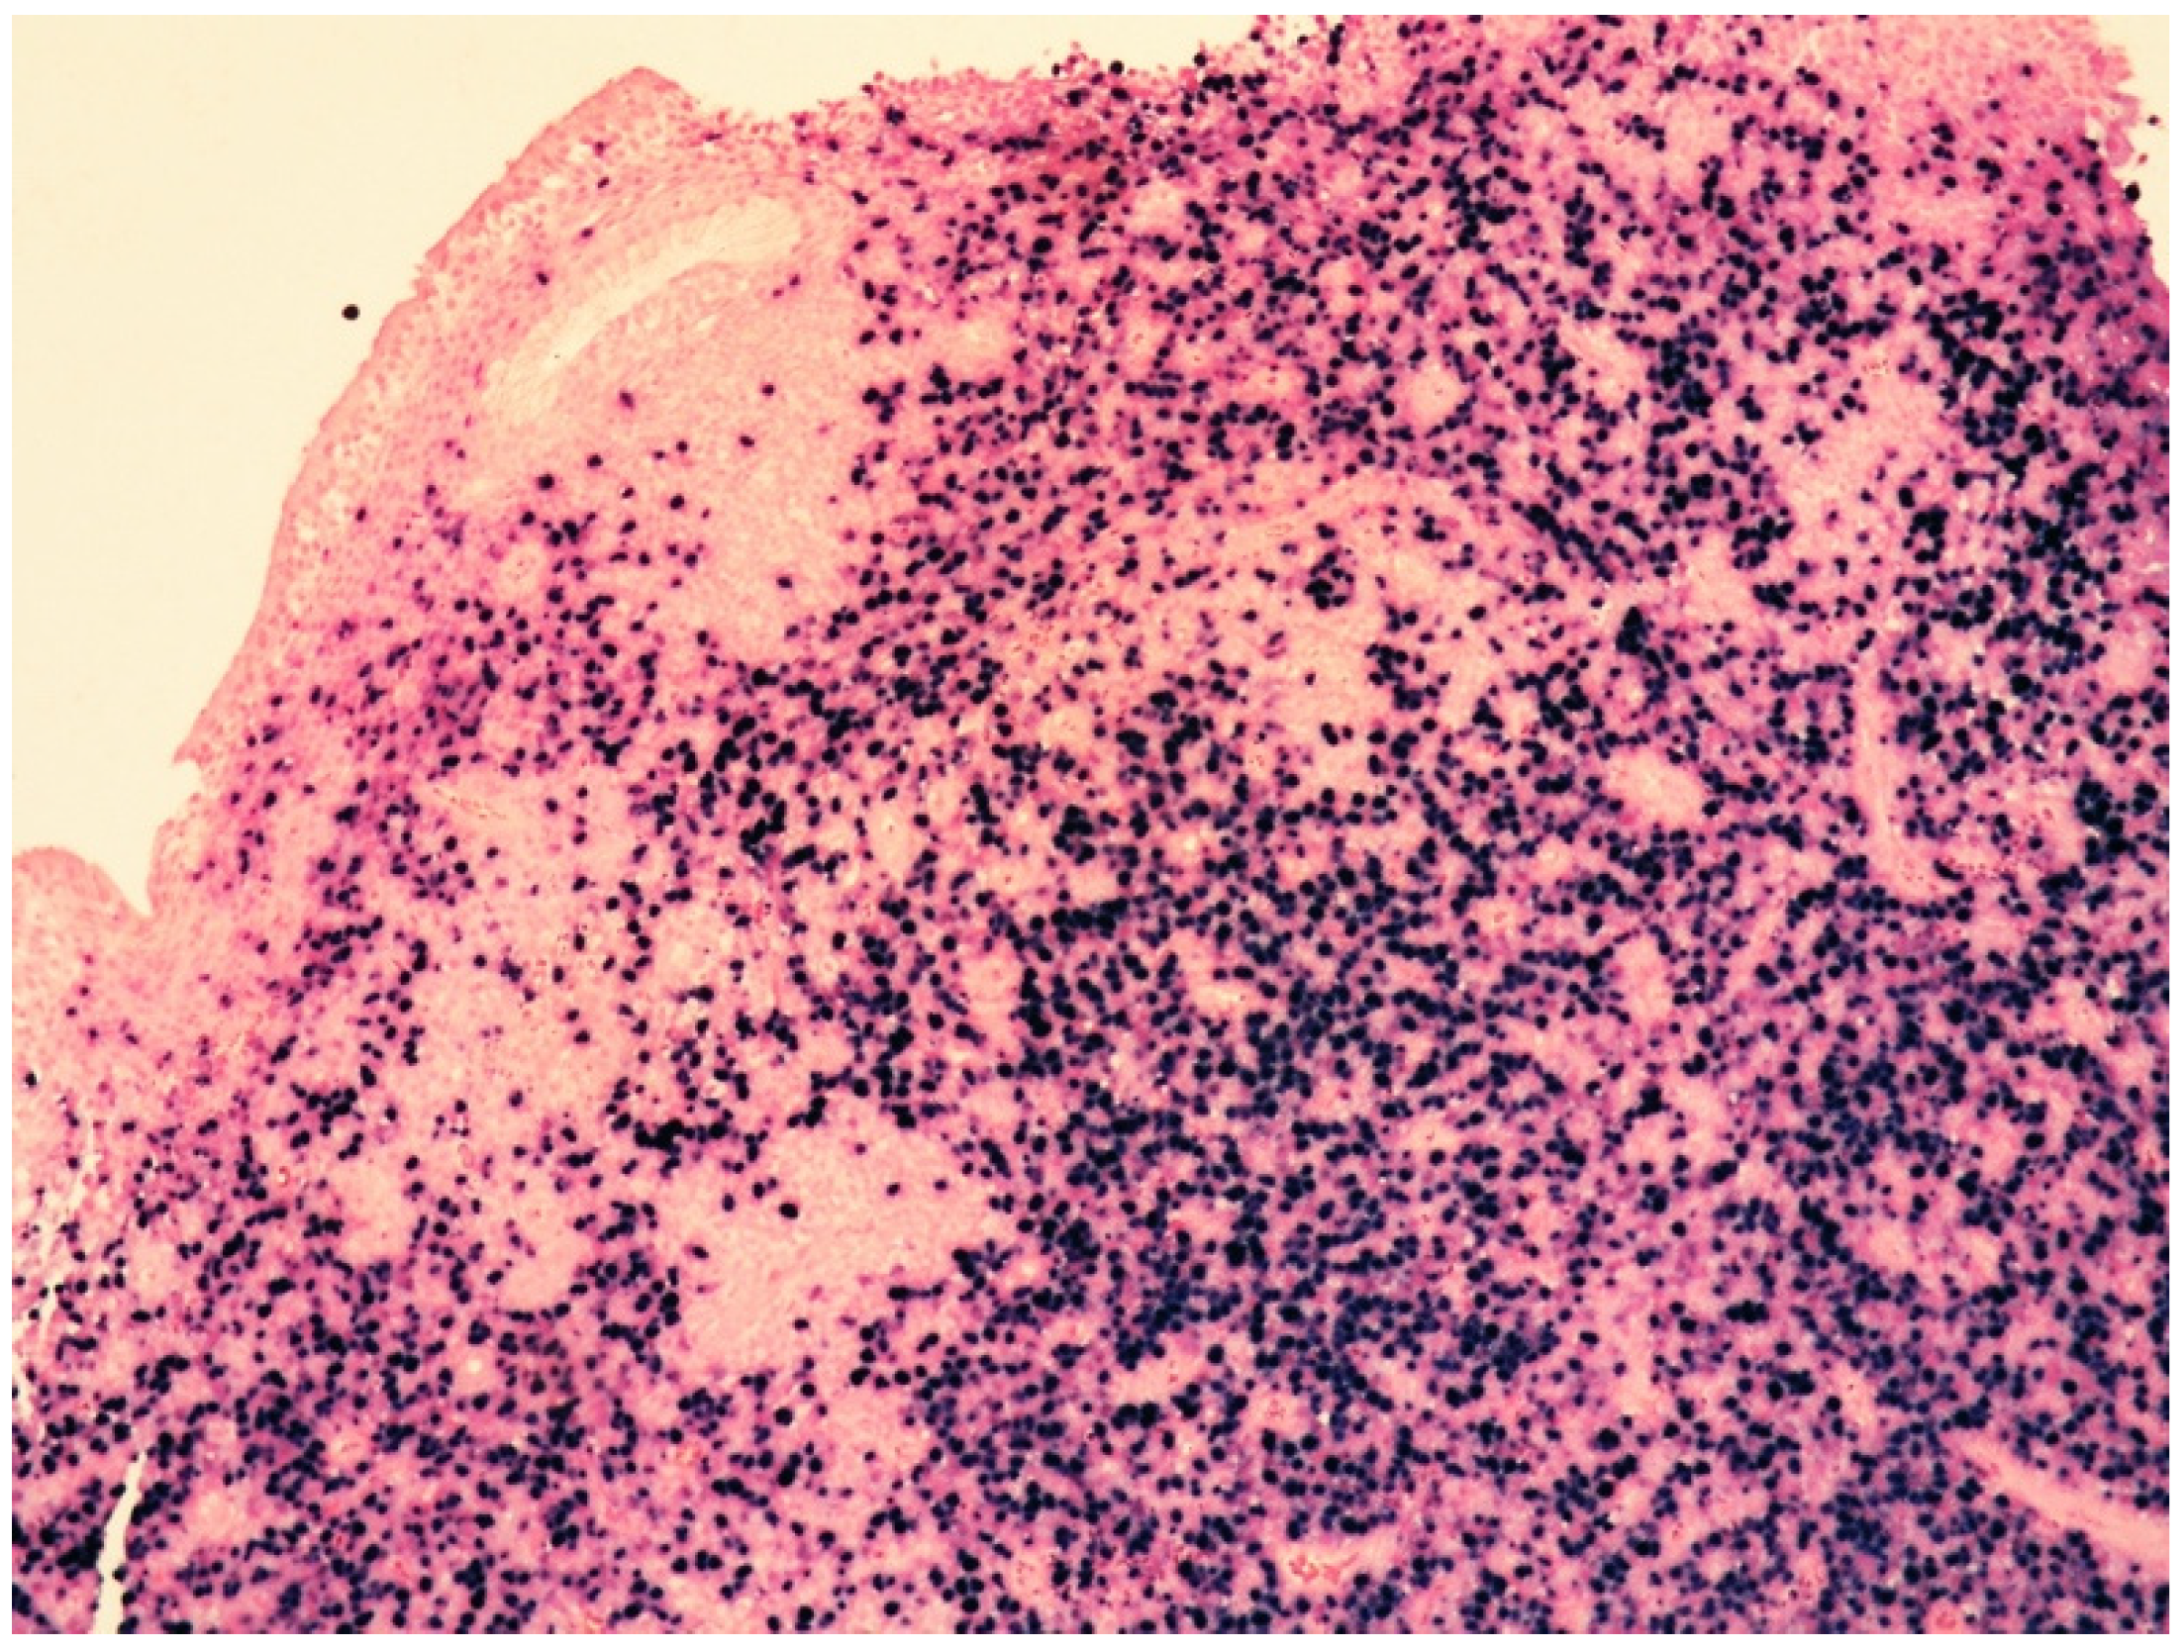

6.2.2. Histology

| Histology | Large-sized cells within medium- to small-sized vessels | Polymorphic cells, clear cytoplasm; inflammatory background, necrosis. Angioinvasive and angiodestructive pattern. | Variable in size from normal granular lymphocytes to large, atypical cells | High-grade morphology (either polymorphic or monomorphic) |